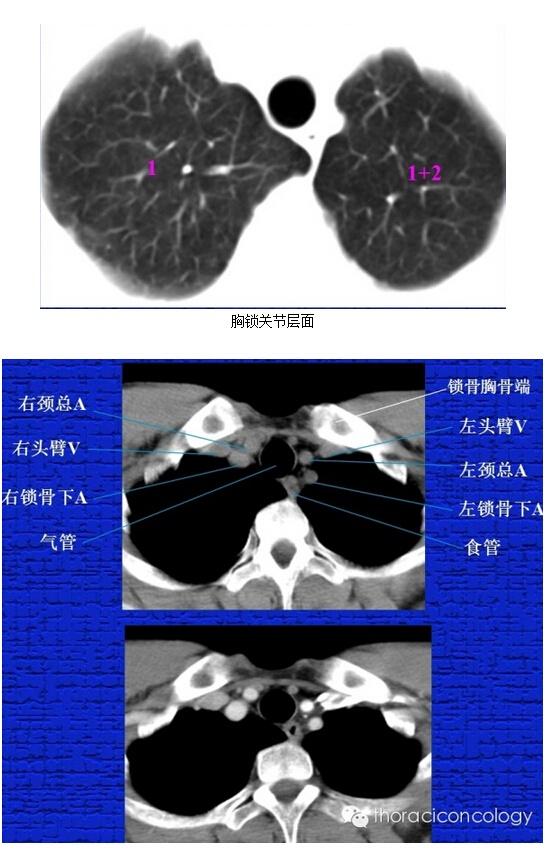

胸部正常ct解剖结构